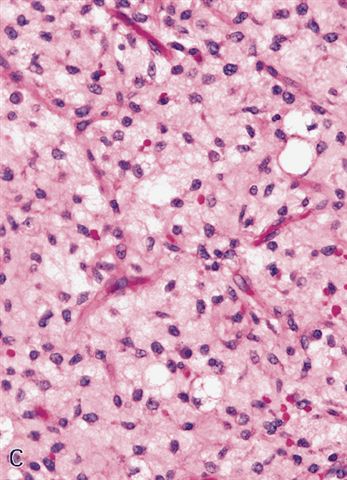

- Low grade

- Paucicellular with monomorphic, stellate or fusiform shaped cells without atypia; striking in their blandness, so much so that any significant pleomorphism should cause one to pause

- Prominent plexiform vasculature (delicate thin walled arborizing and curving capillaries that form a network reminiscent of chicken wire fencing)

- These are striking because of the overall background paucicellularity and are still present in high grade tumors but are much less obvious

- Numerous signet ring lipoblasts, particularly at periphery of lobules

- This imparts a lipoblastoma-like appearance (see Differential diagnosis)

- Mucoid matrix is rich in hyaluronic acid that may form large mucoid pools (so called pulmonary edema pattern)

- Will be positive for stromal mucin stains such as Alcian blue (see Microscopic (histologic) images)

The microscopic image above depicts the histologic appearance of a soft tissue mass resected from the thigh of a 37 year old man and is representative of the entire lesion. Which of the following is true regarding the diagnosis?

D. Majority of cases harbor t(12;16) FUS::DDIT3 gene fusion. The microscopic image depicts a low grade myxoid liposarcoma characterized by a proliferation of bland stellate tumor cells embedded in a myxoid matrix with a prominent plexiform capillary network and scattered signet ring lipoblasts. There is no mitotic activity or pleomorphism. The majority of cases of myxoid liposarcoma harbor a t(12;16) FUS::DDIT3 gene fusion. Answers B and C are incorrect because the t(9;22) EWSR1::NR4A3 gene fusion is characteristic of extraskeletal myxoid chondrosarcoma and the t(7;16) FUS::CREB3L2 gene fusion is characteristic of low grade fibromyxoid sarcoma. Answer E is incorrect because classification of myxoid liposarcoma as high grade requires > 5% of the sampled lesion to consist of a hypercellular round cell component according to the WHO. Cases with borderline round cell component (< 5%) are regarded as having areas of transition, a designation of unclear diagnostic significance. Answer A is incorrect because immunohistochemistry for MDM2 is negative in myxoid liposarcomas.